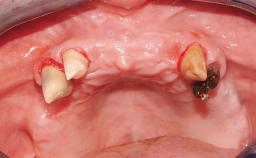

Immediate Loading of Six Implants in the Maxilla and Final Restoration with a Full-Arch CAD/CAM Zirconia FDP

A 63-year-old male patient was referred for a consultation and treatment of partial edentulism in the maxilla. The patient presented with residual anterior teeth and declined a partial removable prosthesis. He reported that the maxillary posterior teeth had been extracted due to mobility and periodontal disease two months before the consultation. The patient’s chief complaint was that his residual maxillary teeth were mobile and that he was unable to chew. The patient’s desire was a stable and comfortable fixed maxillary rehabilitation. The patient was a light smoker (fewer than 10 cigarettes/ day), and his medical history was without significant findings. He was not on any regular medication at the time of consultation. The extraoral examination revealed a normal physiognomy with a correct distribution of the facial thirds. The patient presented a low lip line, and the transition line between teeth and soft tissues was not exposed during a forced smile.

Soft Tissue Anatomy Intact Defective

Bone Volume Horizontally and vertically sufficient Horizontally deficient Deficient vertically or deficient vertically AND horizontally